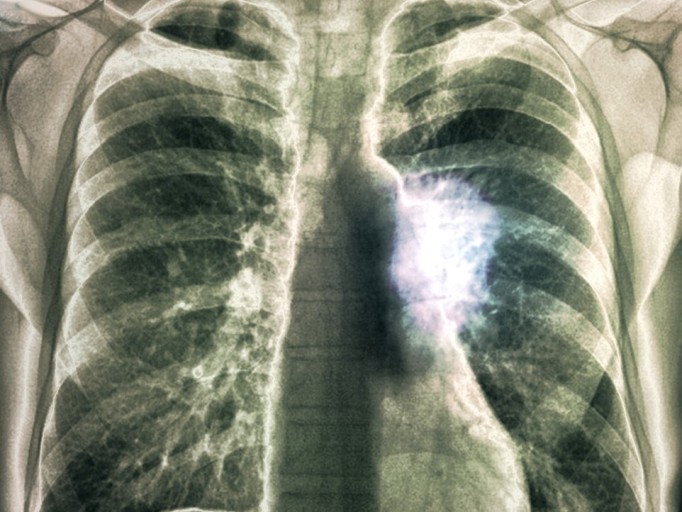

오늘은 우리 몸의 호흡을 책임지는 폐에 대해 이야기하려 합니다. 특히, 폐에 발생하는 악성 종양인 폐암의 초기 증상에 대해 자세히 알아보려 합니다.

폐암 초기증상 폐암은 초기 증상이 감기나 다른 호흡기 질환과 비슷해 간과하기 쉽습니다. 하지만 조기 발견이 치료에 매우 중요하기 때문에, 미묘한 변화라도 놓치지 않는 것이 중요합니다. 지금부터 폐암의 주요 초기 증상들을 꼼꼼히 살펴보고, 건강을 지키는 첫걸음을 함께 시작해 볼까요?

폐암 초기에는 특별한 증상이 없는 경우가 많지만, 암이 진행되면서 다양한 신호를 보낼 수 있습니다. 다음은 폐암 환자들이 흔히 경험하는 10가지 주요 초기 증상입니다.